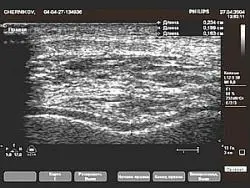

Суглобовий хрящ колінного суглоба. Артроз: висота хряща знижена